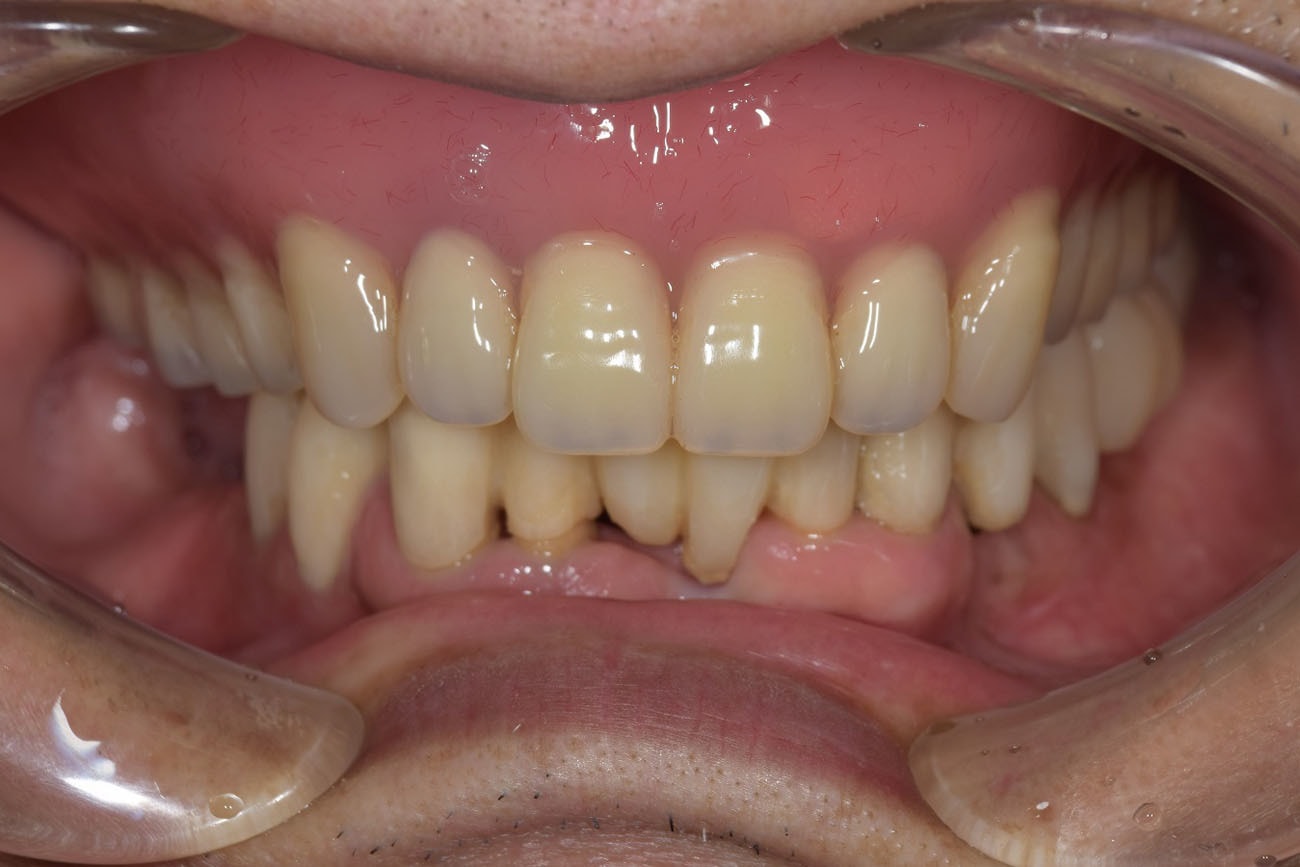

治療後

治療後の写真は、歯周病の基本的な治療と仮の入れ歯と仮歯にてかみ合わせをある程度再建した状態です。ここから更に保存できそうな歯に関しては、歯周病の専門的な手術を受けて頂き、歯周病の治療していくことになります。